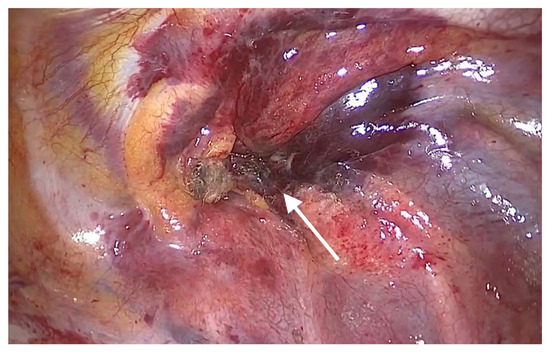

After the insertion of a trocar in the fifth intercostal space on the midaxillary line and that of a thoracoscope, we noticed that bleeding and hematoma occurred in the SVC. The site of perforation was located in the extra-pericardial portion of the SVC.Even after the aspiration of blood at a volume of approximately 700 mL, bleeding was persistently present at the site of perforation in the SVC. This was accompanied by the presence of hematoma in the right brachiocephalic vein (Figure 1). The patient had a gradual decrease in blood pressure. Therefore, the patient received a continuous intravenous infusion of norepinephrine 0.05 μg/kg/min and the crystalloid solution at a rate of 600 mL/hr. For hemostasis, the site of bleeding in the SVC was compressed using a gauze pad for 20 min, followed by the use of an active absorbable collagen hemostat. On noticing that bleeding was discontinued, we performed surgery to remove foreign bodies from the esophagus (Figure 2).

Figure 2. Intraoperative hemostasis at the site of perforation (arrow) of the superior vena cava.